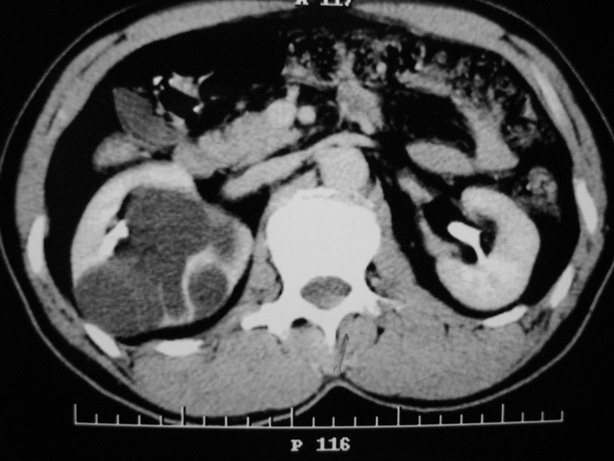

标题: CT10772:男性,48,右肾盂旁多囊性占位!

男性,48,体检发现,平时无症状。

增强:

肾盂旁多囊性占位,有实性成分,增强有轻度强化,收集期病变内无造影剂显影。诊断肾盂旁囊肿,有实性成分无法解释,查书后诊断为:多房性囊性肾瘤!!不知大家同意否?????????对本病知道不多,望大家不吝赐教!!

右肾多发囊性低密度影,囊内有增强的隔及实性组织,考虑囊性肾癌。